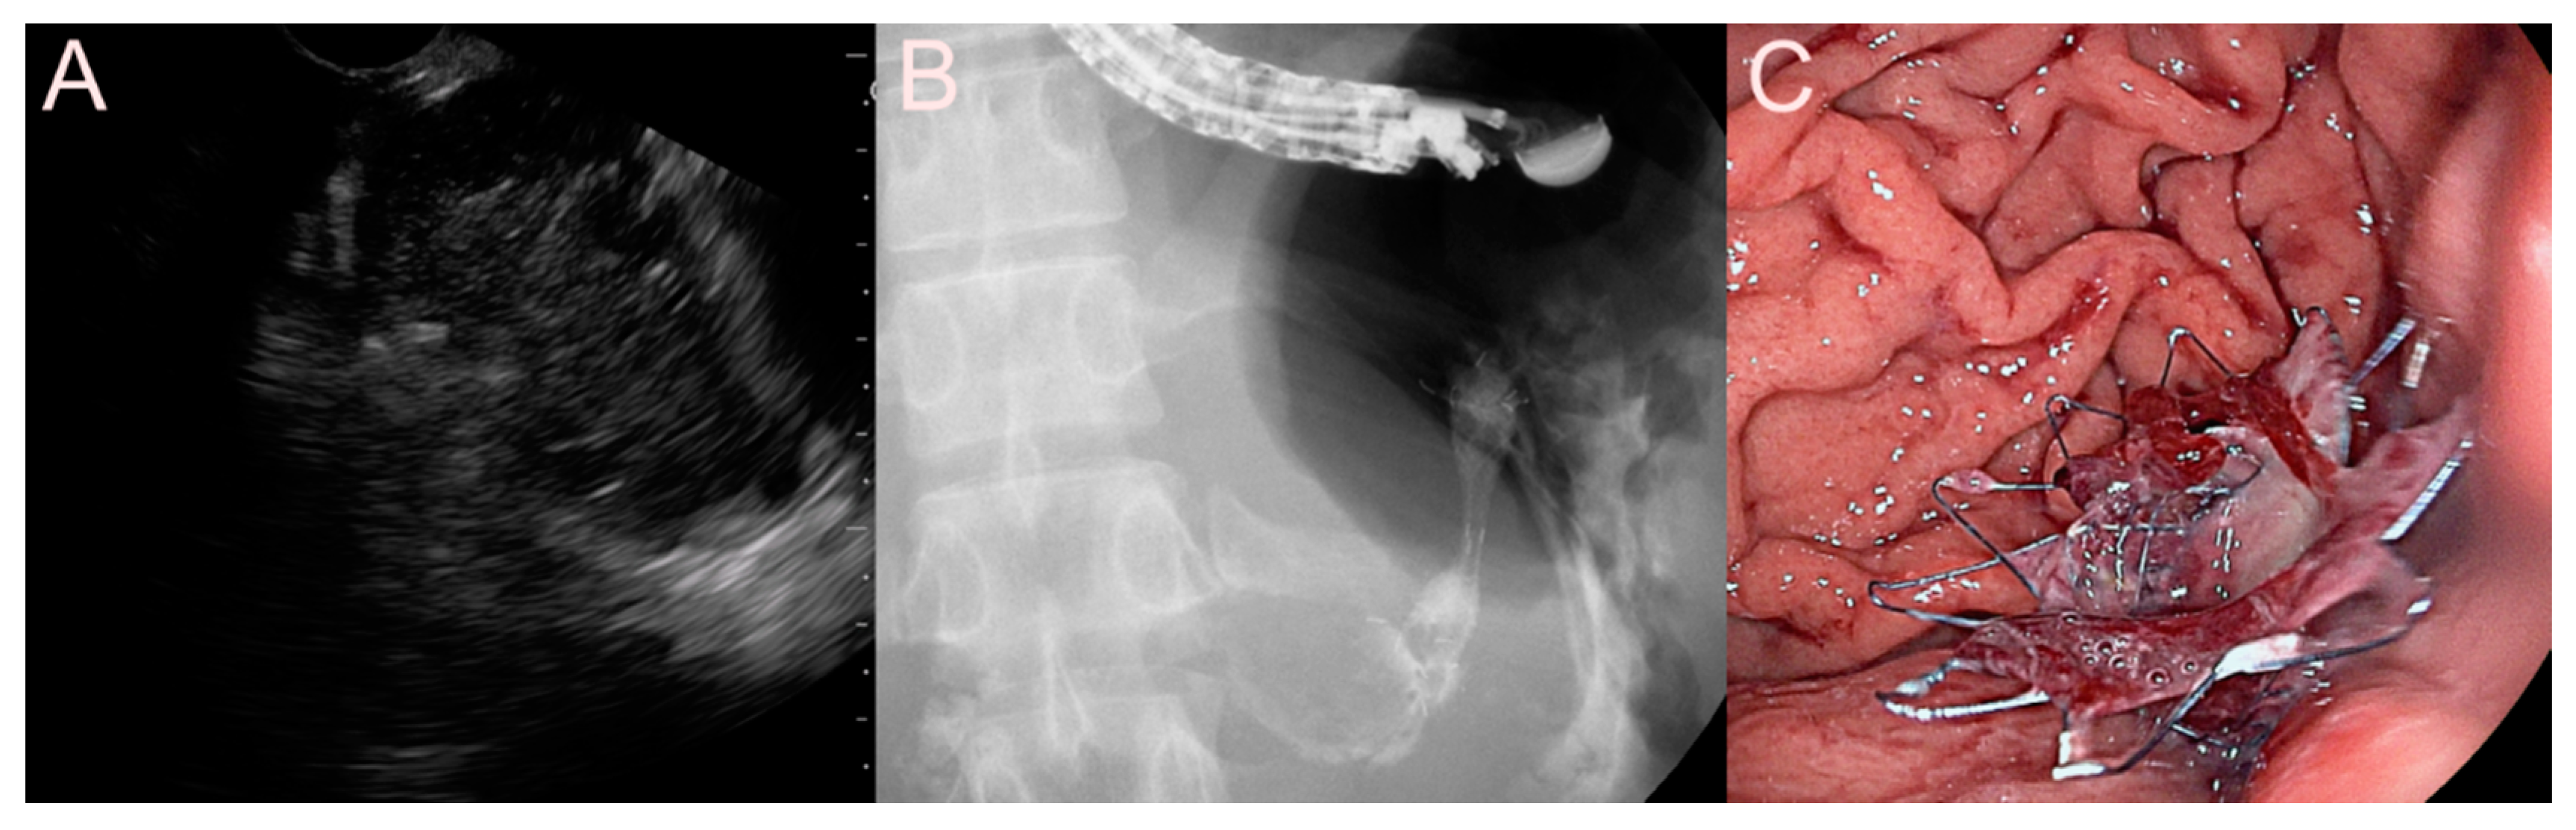

2.4. Stent for EUS-Guided Pancreatic Duct (PD) Drainage

2.4.1. Use of the Plastic Stent

2.4.2. Use of the SEMS